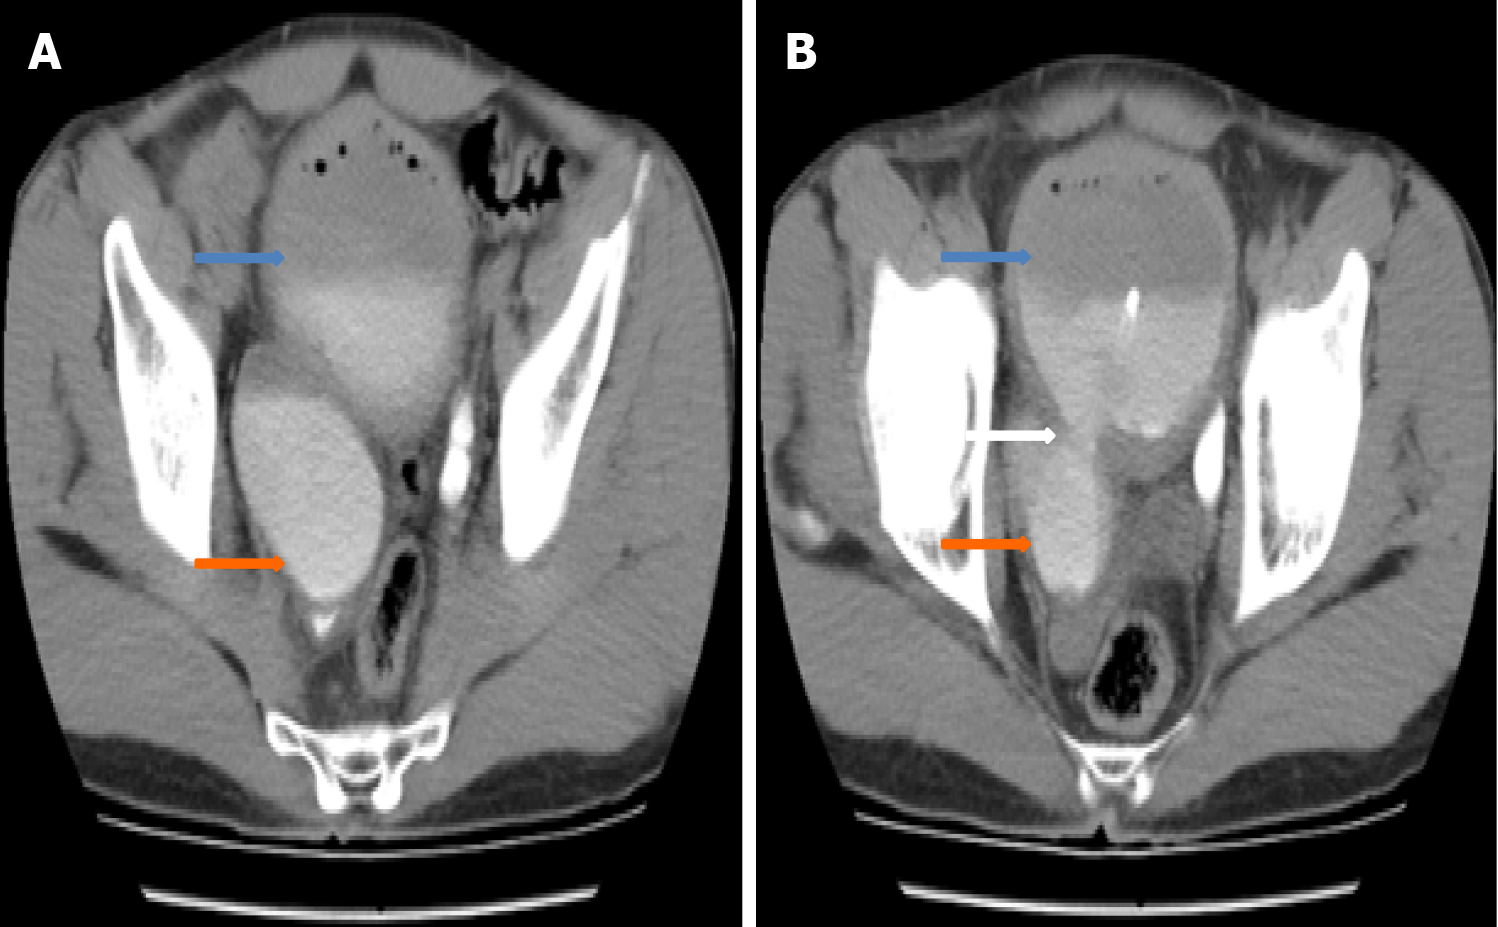

Figure 6 Computerised tomographic imaging shows the paraureteral diverticulum illustrated in Figure 2.

A: Axial view; B: Axial view at the level of paraureteral diverticulum neck.